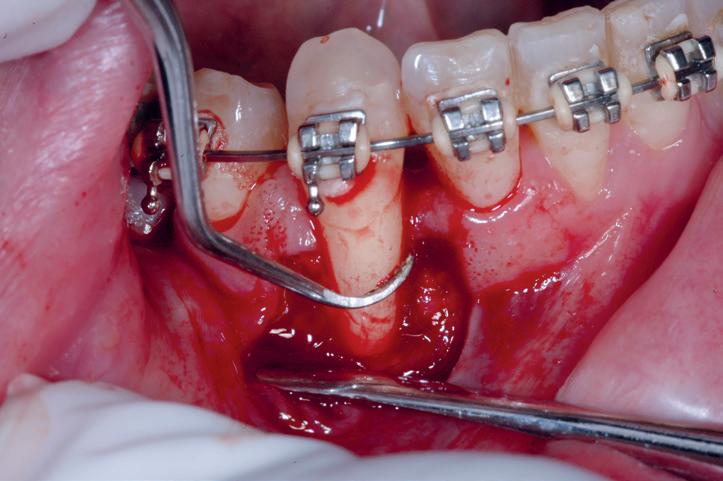

Preparação do leito recetor

O procedimento cirúrgico inicia-se com a preparação do leito recetor, permitindo um período de tempo adequado para a hemóstase do leito e minimizando o intervalo de tempo

Figs.1 a 4. Recessões gengivais.

Figs. 5 e 6. Preparação do leito recetor.

entre a remoção e colocação do enxerto. O epitélio, tecido conjuntivo e fibras musculares do local recetor são dissecadas até ao periósteo. A camada de tecido mole remanescente forma a base imóvel, que permite a imobilização do enxerto e reduz a contração pós-operatória do mesmo (Sullivan e Atkins, 1968), (figs. 5 e 6).

A superfície do leito deve ser plana para prevenir a acumulação de sangue e a formação de um coágulo nas zonas irregulares. Após a preparação, uma gaze embebida com solução salina deve colocar-se sobre o leito para controlar a hemorragia (Sullivan e Atkins, 1968).